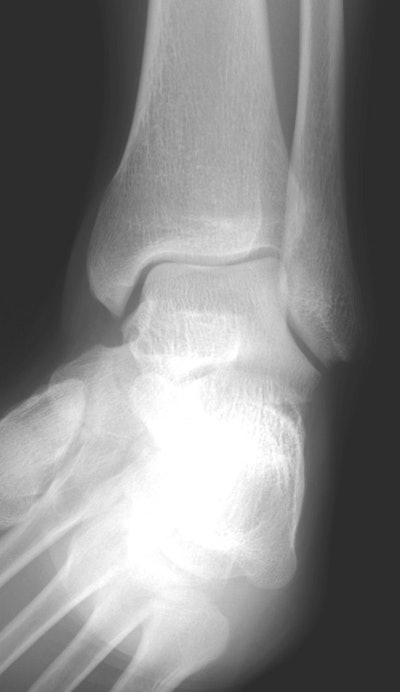

Wednesday: Mortise view of the ankle.